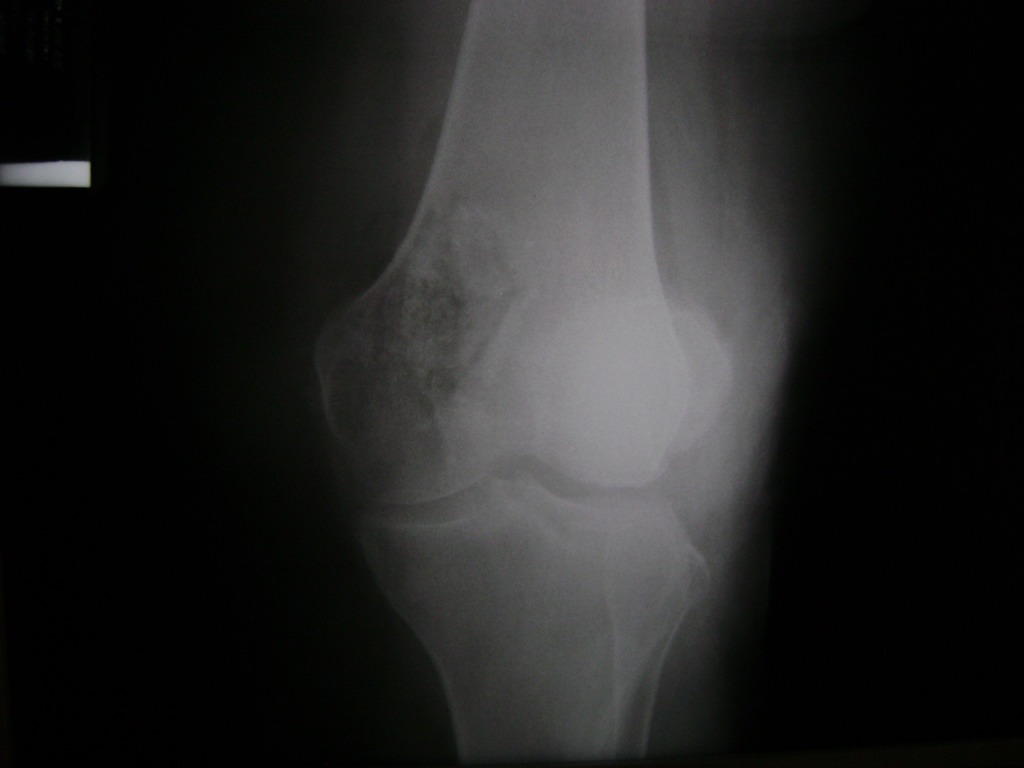

Cirugías de Rodillas